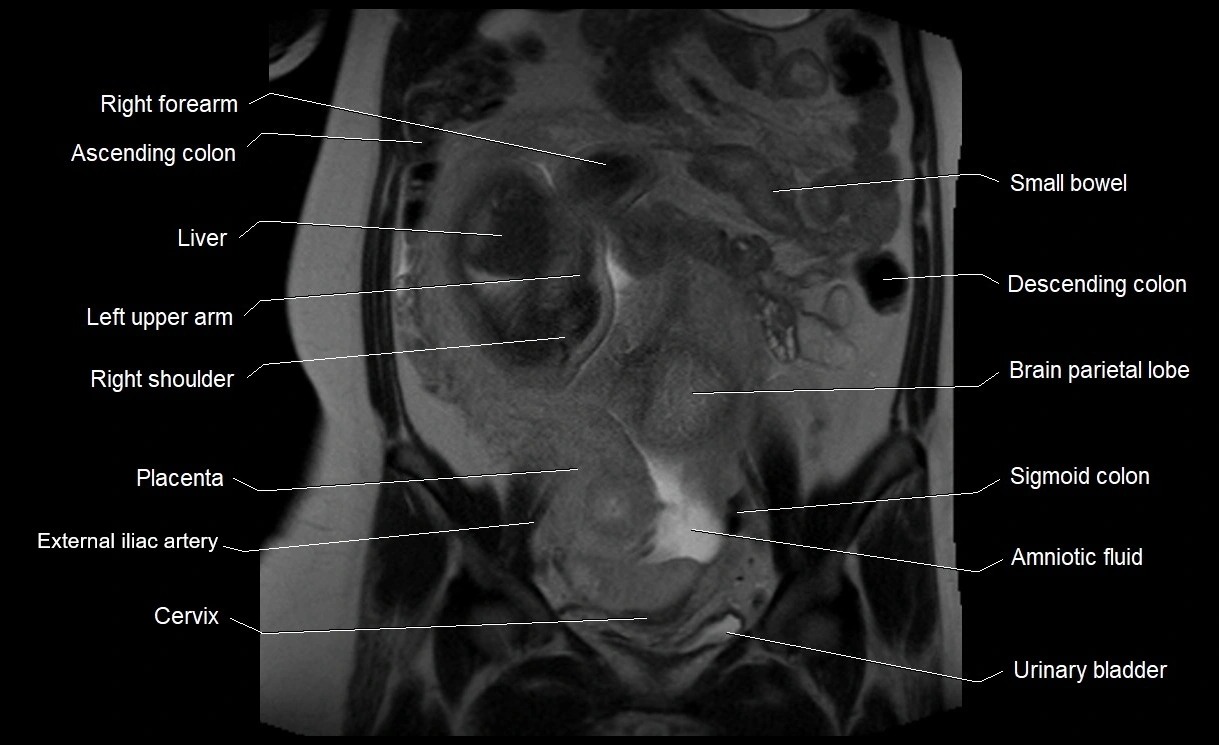

Relations

• Enclosed within the amniotic sac, bounded by the amnion and chorion

• Surrounds and cushions the developing fetus

• In continuity with maternal circulation through placental and transmembrane exchanges

MRI Appearance

T2 HASTE (T2 GRE):

• Amniotic fluid shows very bright hyperintense signal

• Provides natural contrast against fetus and placenta

• Small particles (vernix) may appear as scattered hypointense foci within bright fluid

MRI image

image